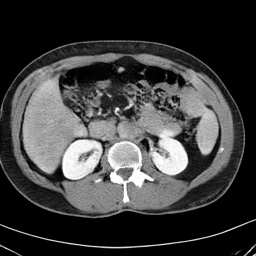

In many clinical settings, the use of both Computed Tomography (CT) and Magnetic Resonance (MRI) is necessary to pursue a thorough understanding of the patient's anatomy and to plan a suitable therapeutical strategy; this is often the case in MRI-based radiotherapy, where CT is always necessary to prepare the dose delivery, as it provides the essential information about the radiation absorption properties of the tissues. Sometimes, MRI is preferred to contour the target volumes. However, this approach is often not the most efficient, as it is more expensive, time-consuming and, most importantly, stressful for the patients. To overcome this issue, in this work, we analyse the capabilities of different configurations of Deep Learning models to generate synthetic CT scans from MRI, leveraging the power of Generative Adversarial Networks (GANs) and, in particular, the CycleGAN architecture, capable of working in an unsupervised manner and without paired images, which were not available. Several CycleGAN models were trained unsupervised to generate CT scans from different MRI modalities with and without contrast agents. To overcome the problem of not having a ground truth, distribution-based metrics were used to assess the model's performance quantitatively, together with a qualitative evaluation where physicians were asked to differentiate between real and synthetic images to understand how realistic the generated images were. The results show how, depending on the input modalities, the models can have very different performances; however, models with the best quantitative results, according to the distribution-based metrics used, can generate very difficult images to distinguish from the real ones, even for physicians, demonstrating the approach's potential.